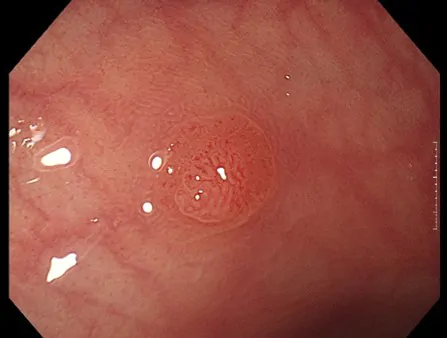

NBI(狭帯域光観察)

がんの増殖には血管からの栄養補給を必要とするため、病変の近くの粘膜には、小さな血管が集まりやすくなります。そのため、この小さな血管の集まりをいち早く発見することが、がんなどの病変の早期発見には重要です。

そのために用いられる技術が、「NBI(Narrow Band Imaging)」です。NBIは、血液中のヘモグロビンに吸収されやすい紫と緑の2つの特殊な光を照らすことで、粘膜表層の毛細血管やそのパターンなどが強調して鮮明に表示される観察技術です。これにより、通常光による観察では見えづらかったがんなどの病変の早期発見に貢献することが期待されます。

また、最適な治療判断には病変診断も重要となります。NBIは血管や粘膜の詳しい観察をサポートし、その診断にも貢献することが期待されます。

大腸カメラの症例